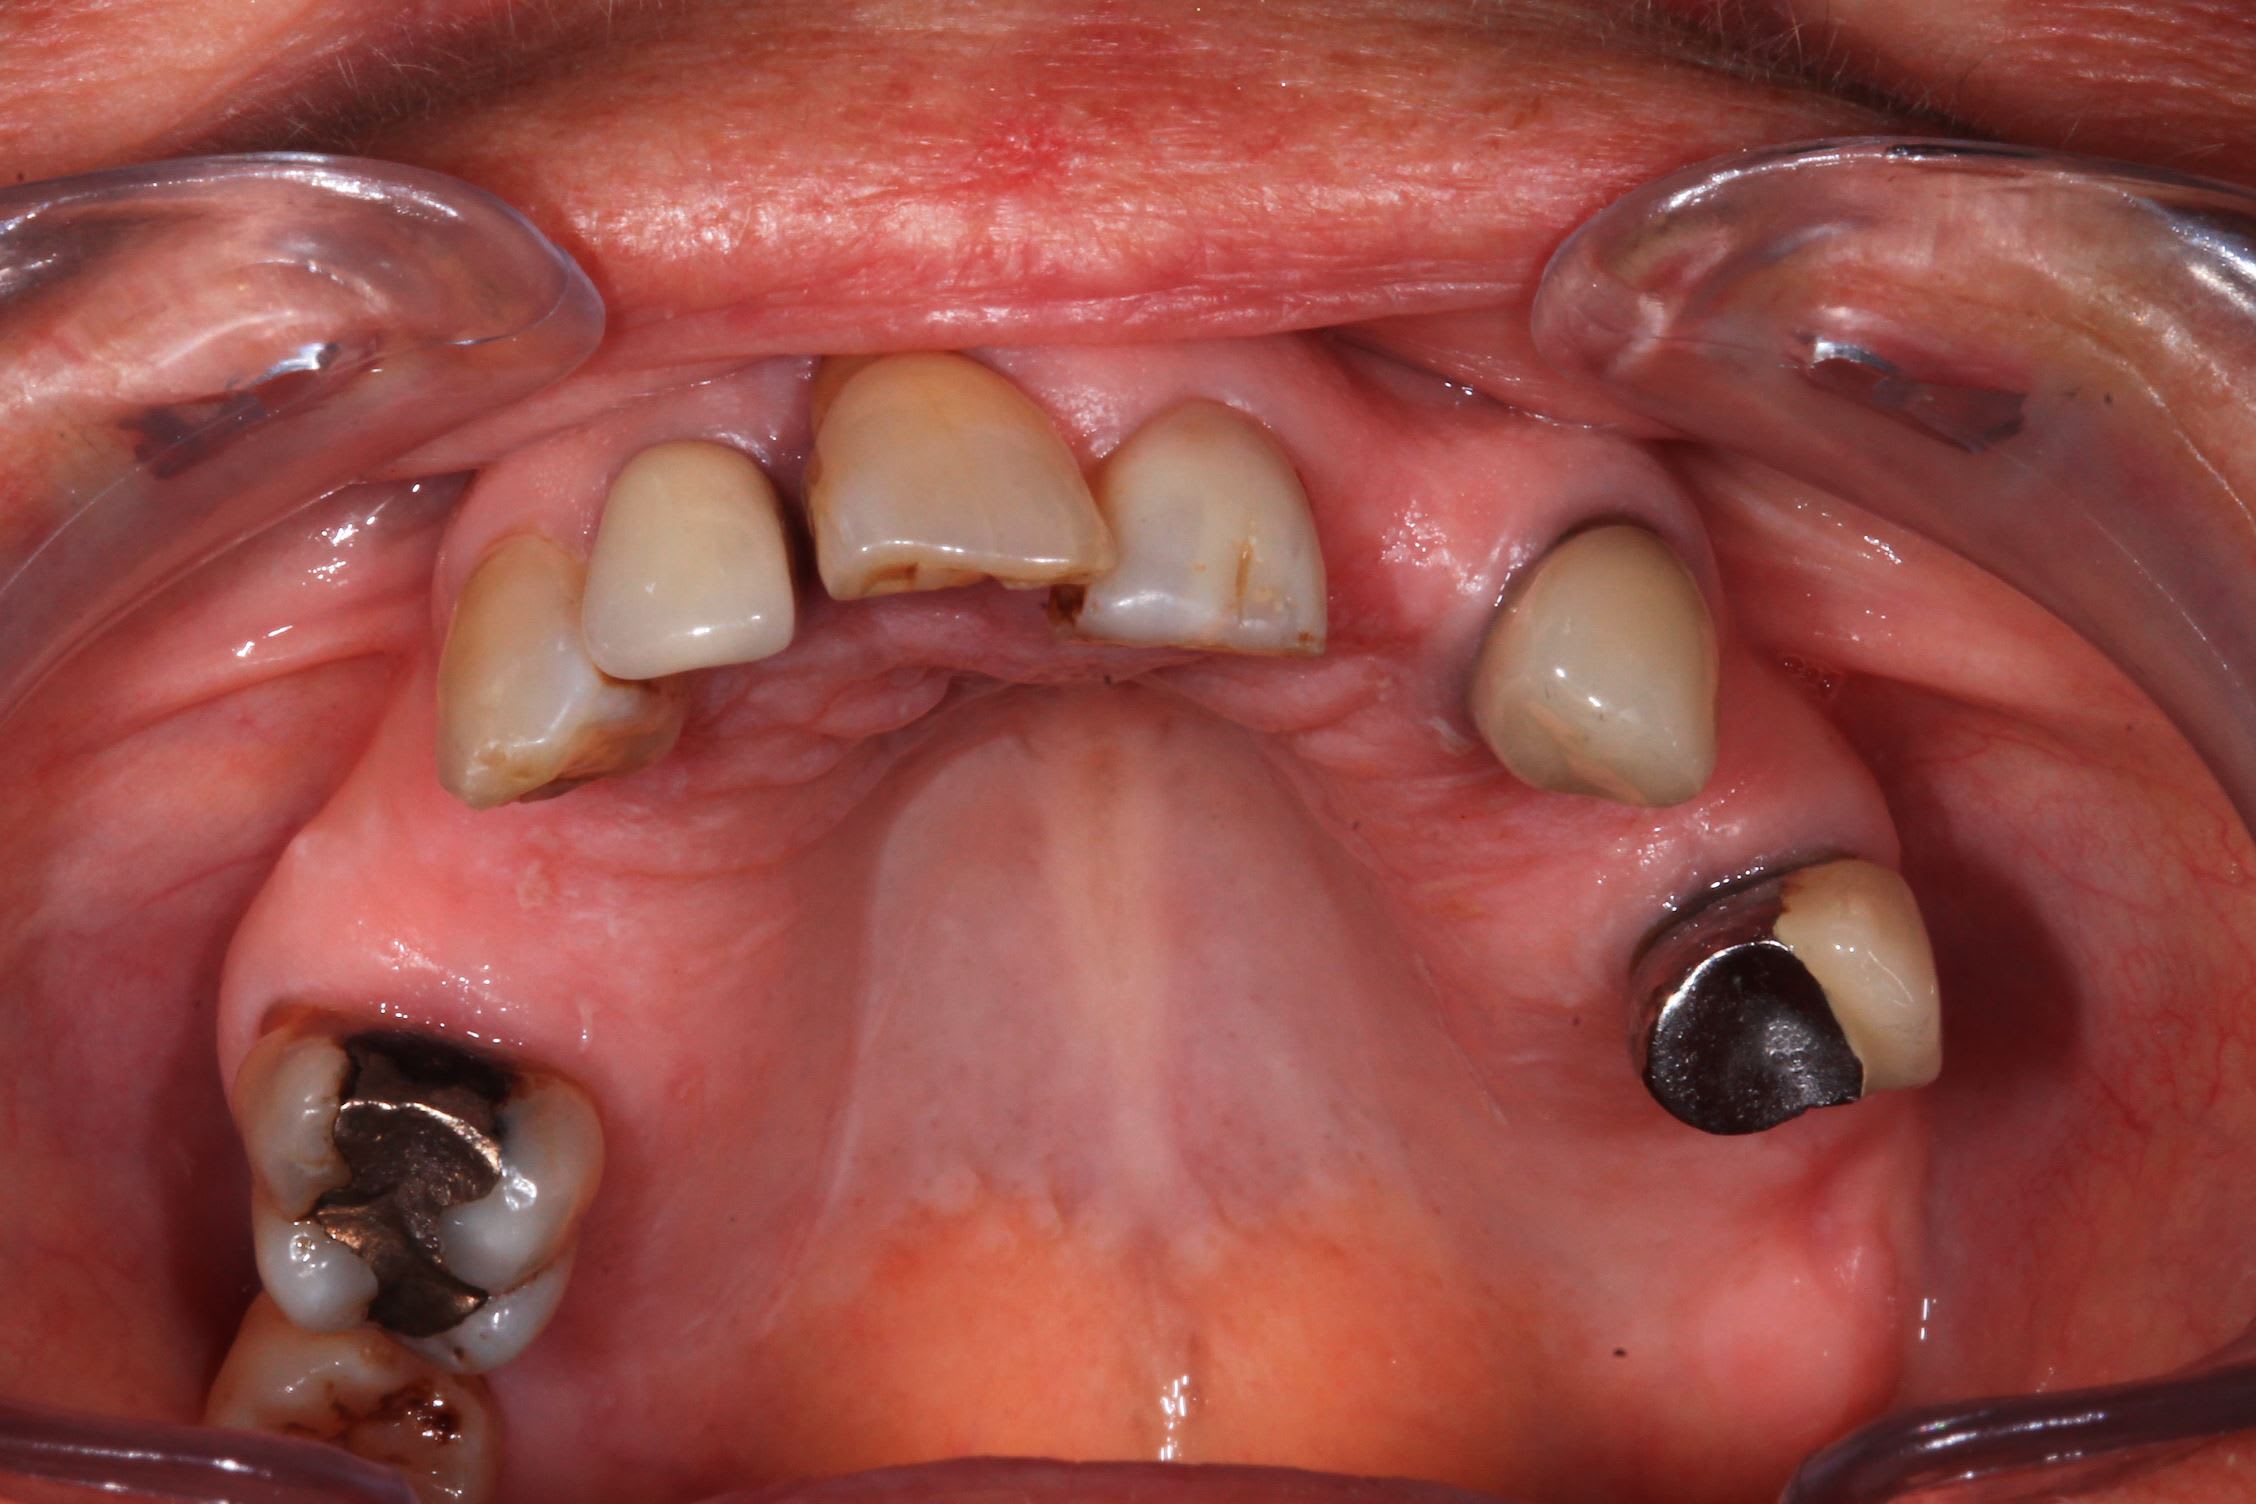

Cas 1 : Implants de 14 et 12 mm, tous en appuis bi-corticale, patiente agé, emergence des implants distaux au niveau des 5. zone assez cicatrisés pour les implants , sauf pour 12 mais qui a un bon ancrage palatin. Pas trop de solution pour en mette 6. rien en distal. Bon cas de AO4 a mon avis.

Le cas de la semaine derniere : implants super stable. Premier coup de bistouri a 9h45, patiente sortie à 13h. J'ai galéré avec un satané apex cassé et des canines rebelles : presque 3/4 h pour les extractions !

la suite. Photo post op immédiate et a trois jours.